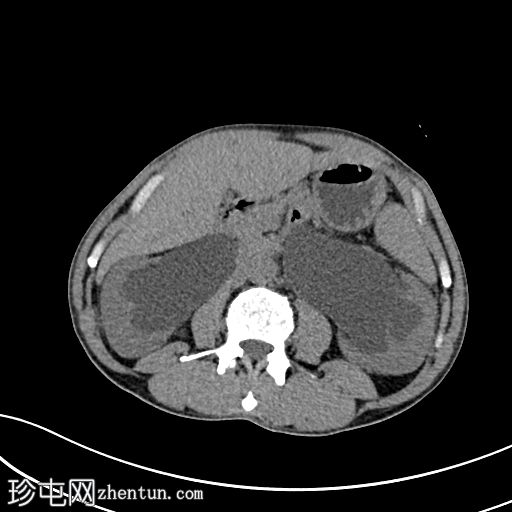

轴位

平扫

膀胱内可见一枚较大的高密度结石(轴位、冠状位、矢状位),大小约8 × 5.6 × 5.1 cm,伴膀胱壁弥漫性增厚和小憩室。

双侧中重度输尿管肾积水,肾实质厚度减薄,左侧更为明显。双侧输尿管迂曲(右侧、左侧),前列腺尿道轻度扩张。双侧未见肾内或输尿管结石。

本病例展示了一例巨大的膀胱结石导致慢性膀胱出口梗阻,并继发双侧输尿管肾积水。